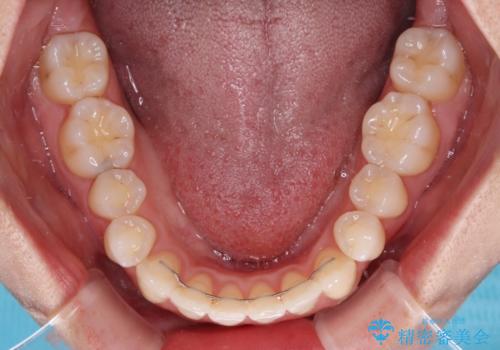

急速拡大装置により骨格はある程度改善されましたが、奥歯の咬み合わせ改善に非常に時間がかかってしまいました。

デコボコを改善させるだけでなく、しっかりとした咬合状態を獲得することができ、患者様には大変満足していただけました。